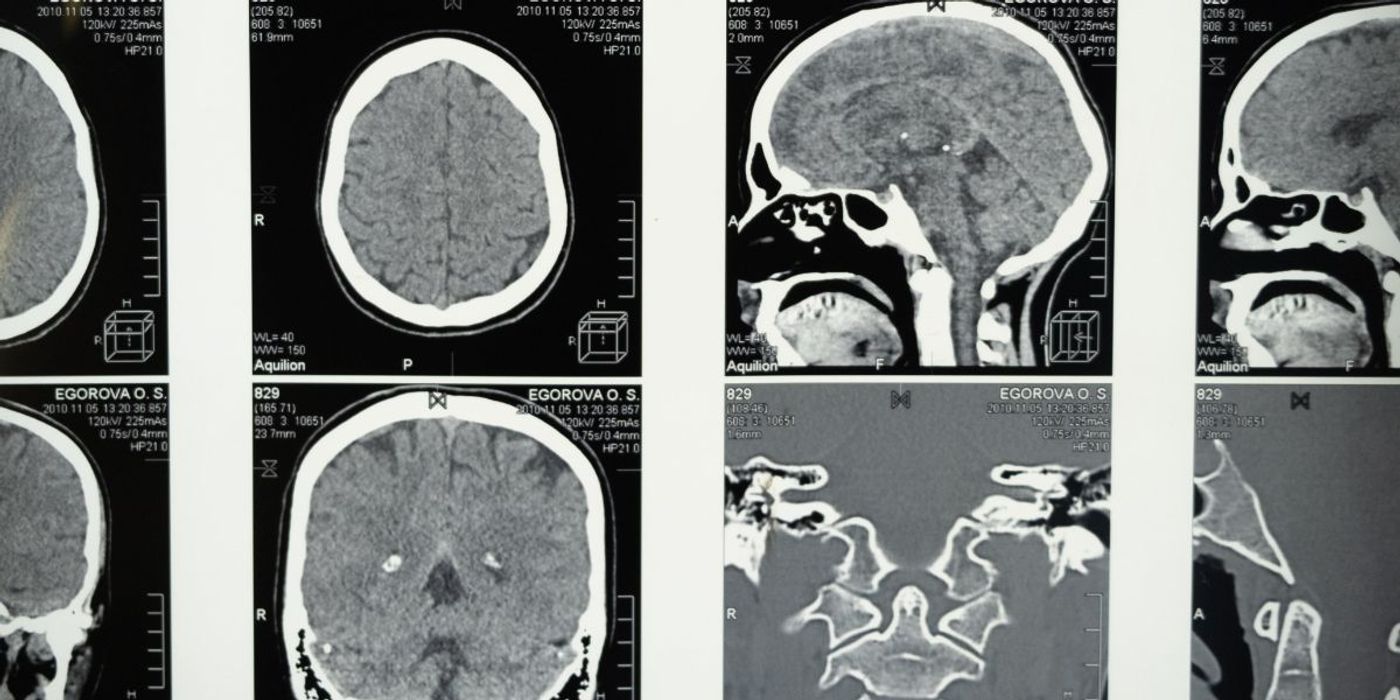

Multiple studies suggest that the insula- an area located deeply within the brain- is critical for nociception and pain experience. In the current study, the researchers thus sought to see whether targeting the insula with focused ultrasound could ease pain. To do so, they recruited 23 healthy participants. They applied heat to the back of their hands to induce pain while delivering focused ultrasound waves to their insula guided by magnetic resonance imaging (MRI). They also monitored participant's heart rates and heart rate variability, and asked them to rate their pain perception on a scale of zero to nine.